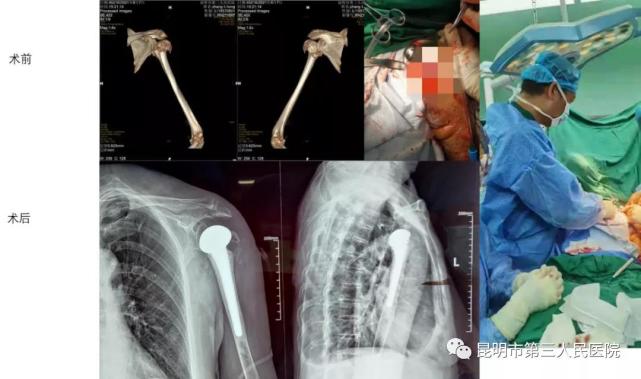

今天要跟大家讲的就是市三院骨科开展的首例人工肩关节置换术。2021年8月7日,市三院骨科收治了一例64岁的女性患者,因摔伤左肩导致肱骨近端骨折(Neer分型:四部分骨折),而且患者同时还合并类风湿性关节炎、重度骨质疏松等多种基础疾病,常规的骨折内固定术失败的可能性较大,在与患者及家属充分沟通后,寸新华主任团队决定为患者实施人工肩关节置换术。

患者入院时左肩疼痛、肿胀、畸形、活动受限,诊断为左肱骨上段粉碎性骨折,断端略内侧成角,内背侧移位,左肩关节半脱位。经术前准备后于8月12日接受手术,寸主任取上臂Henry切口入路,逐层分离至显露骨折远段,曲屈肘关节探查,清除断端积血、骨痂及碎骨块,清理肱骨髓腔,选择大小合适的肱骨柄假体试模及肱骨头置入测试关节的稳定性,然后在髓腔内填充骨水泥,最后放置测试好的肱骨柄和肱骨头行关节复位,手术顺利完成,经术后随访观察,治疗效果良好。